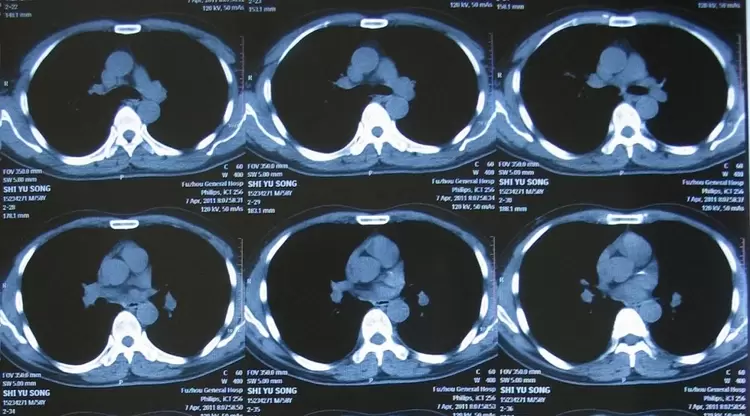

谷歌人工智能对医疗系统学习,都是利用成像数据进行深度学习,其速度和判断是优于人工医生的。比如针对人眼睛的视网膜图像,相比于其他皮肤或者病理成像,其变异性小,数据更好,通过对海量图片的自我学习与记忆,人工智能计算进行医疗辅助诊断。计算机的深度学习就会表现得更好,但在临床诊断过程中,系统限制就变得更加明显,影响到诊断结果和效能。